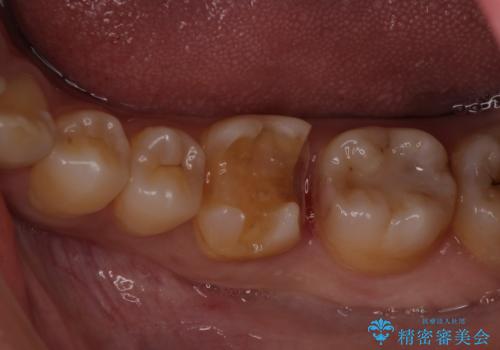

虫歯の大きさや形を加味して、1番奥を保険治療、奥から2番目をセラミック治療で行うことになりました。

ご来院当初、患者様は1番奥歯のセラミック治療をご希望されてました。しかし、しっかり診査をして1本手前の歯を治療した方が良いとご提案させて頂きました。

また、奥歯が虫歯になりやすい原因として夜間の歯ぎしりで、歯に小さいヒビが入っている疑いがありました。就寝時マウスピースを使用して予防して頂くこともご提案し、患者様には大変満足して頂きました。